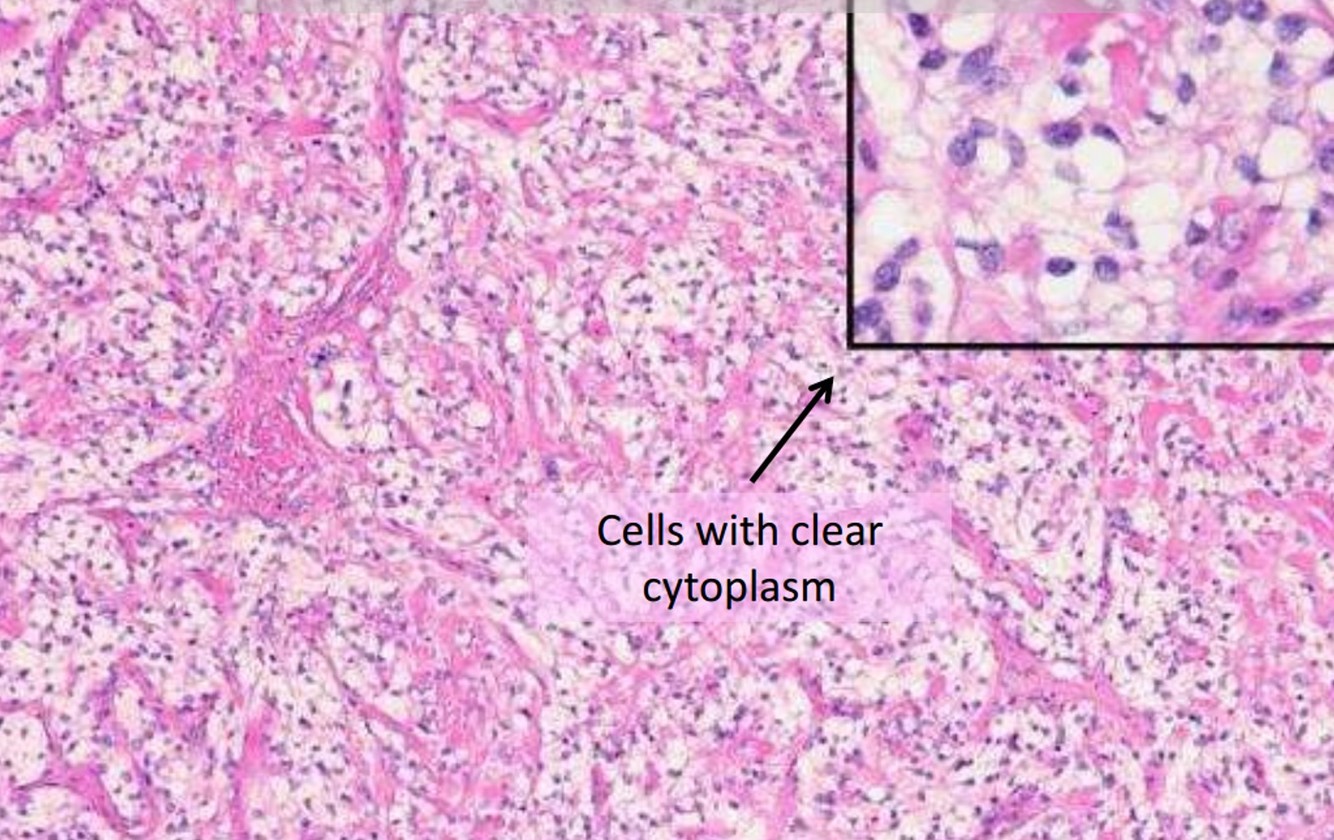

Clear Cell Meningioma